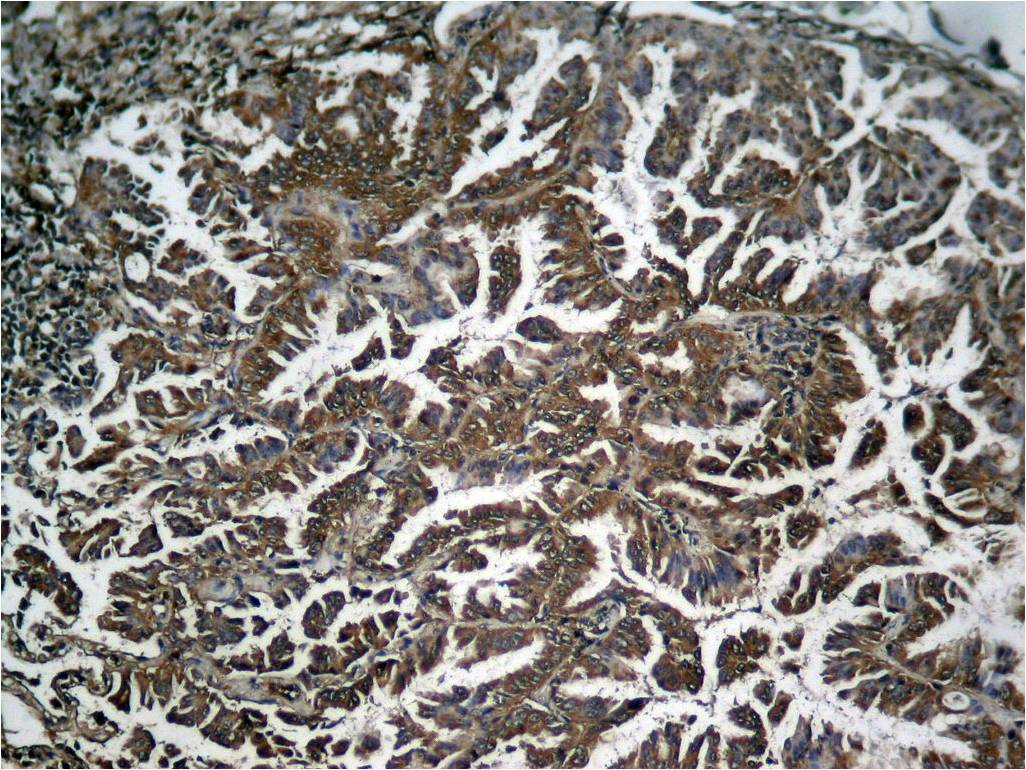

Product information "Anti-phospho-NFkB p65 (Ser536)"

| Application: | ICC, IF, IHC (paraffin), WB |